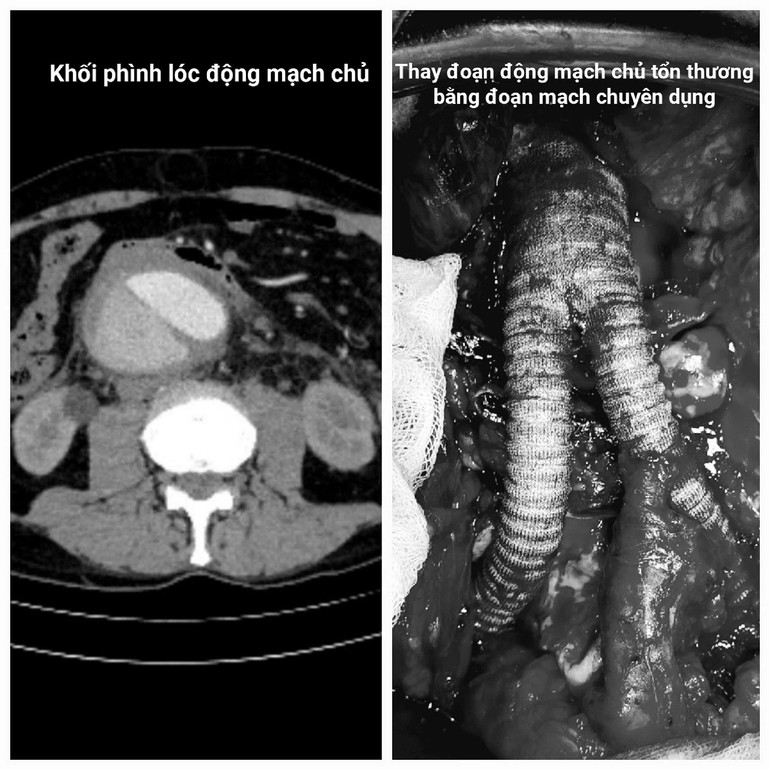

Tại đây, hàng loạt xét nghiệm chuyên sâu, đặc biệt là chụp cắt lớp vi tính (CT) đã phát hiện thảm kịch kép: Không chỉ lóc tách phức tạp, ông Janusz còn mang trong bụng một "quả bom nổ chậm" - khối phình động mạch chủ bụng khổng lồ, đường kính lên tới 9cm (gấp 3 lần bình thường), đang có dấu hiệu vỡ, máu tụ sau phúc mạc.

Tiến sĩ, bác sĩ Ngô Gia Khánh, Trưởng khoa Phẫu thuật Lồng ngực và Mạch máu nhấn mạnh, đây là tình trạng cực kỳ nguy hiểm. Người bệnh có thể tử vong tức thì do sốc mất máu ồ ạt nếu khối phình vỡ hoàn toàn. Chỉ định phẫu thuật cấp cứu thay đoạn động mạch chủ bị tổn thương là bắt buộc để giành giật sự sống.

Diễn biến trong phòng mổ còn căng thẳng hơn dự đoán. Ngay khi mở bụng, ê-kip phẫu thuật đối mặt với tình huống nguy hiểm: Khối phình khổng lồ đã vỡ, máu tràn vào khoang sau phúc mạc. Thời gian tính bằng giây.

Với bản lĩnh và tay nghề dày dặn kinh nghiệm được đúc rút từ hàng nghìn ca mổ phức tạp, các phẫu thuật viên của Khoa Phẫu thuật Lồng ngực và Mạch máu đã nhanh chóng kiểm soát được điểm vỡ, kẹp clamp cầm máu tạm thời.

Điều đặc biệt là các phẫu thuật viên làm được điều này trong khi vẫn bảo tồn tối đa các nhánh động mạch thận và động mạch mạc treo tràng dưới - yếu tố sống còn để người bệnh không rơi vào suy đa tạng sau này.

Sau đó, các bác sĩ tiến hành quá trình thay thế hoàn hảo đoạn động mạch chủ-chậu bị tổn thương bằng một đoạn mạch máu nhân tạo. Từng đường khâu nối mạch máu tỉ mẩn, chính xác dưới kính vi phẫu.